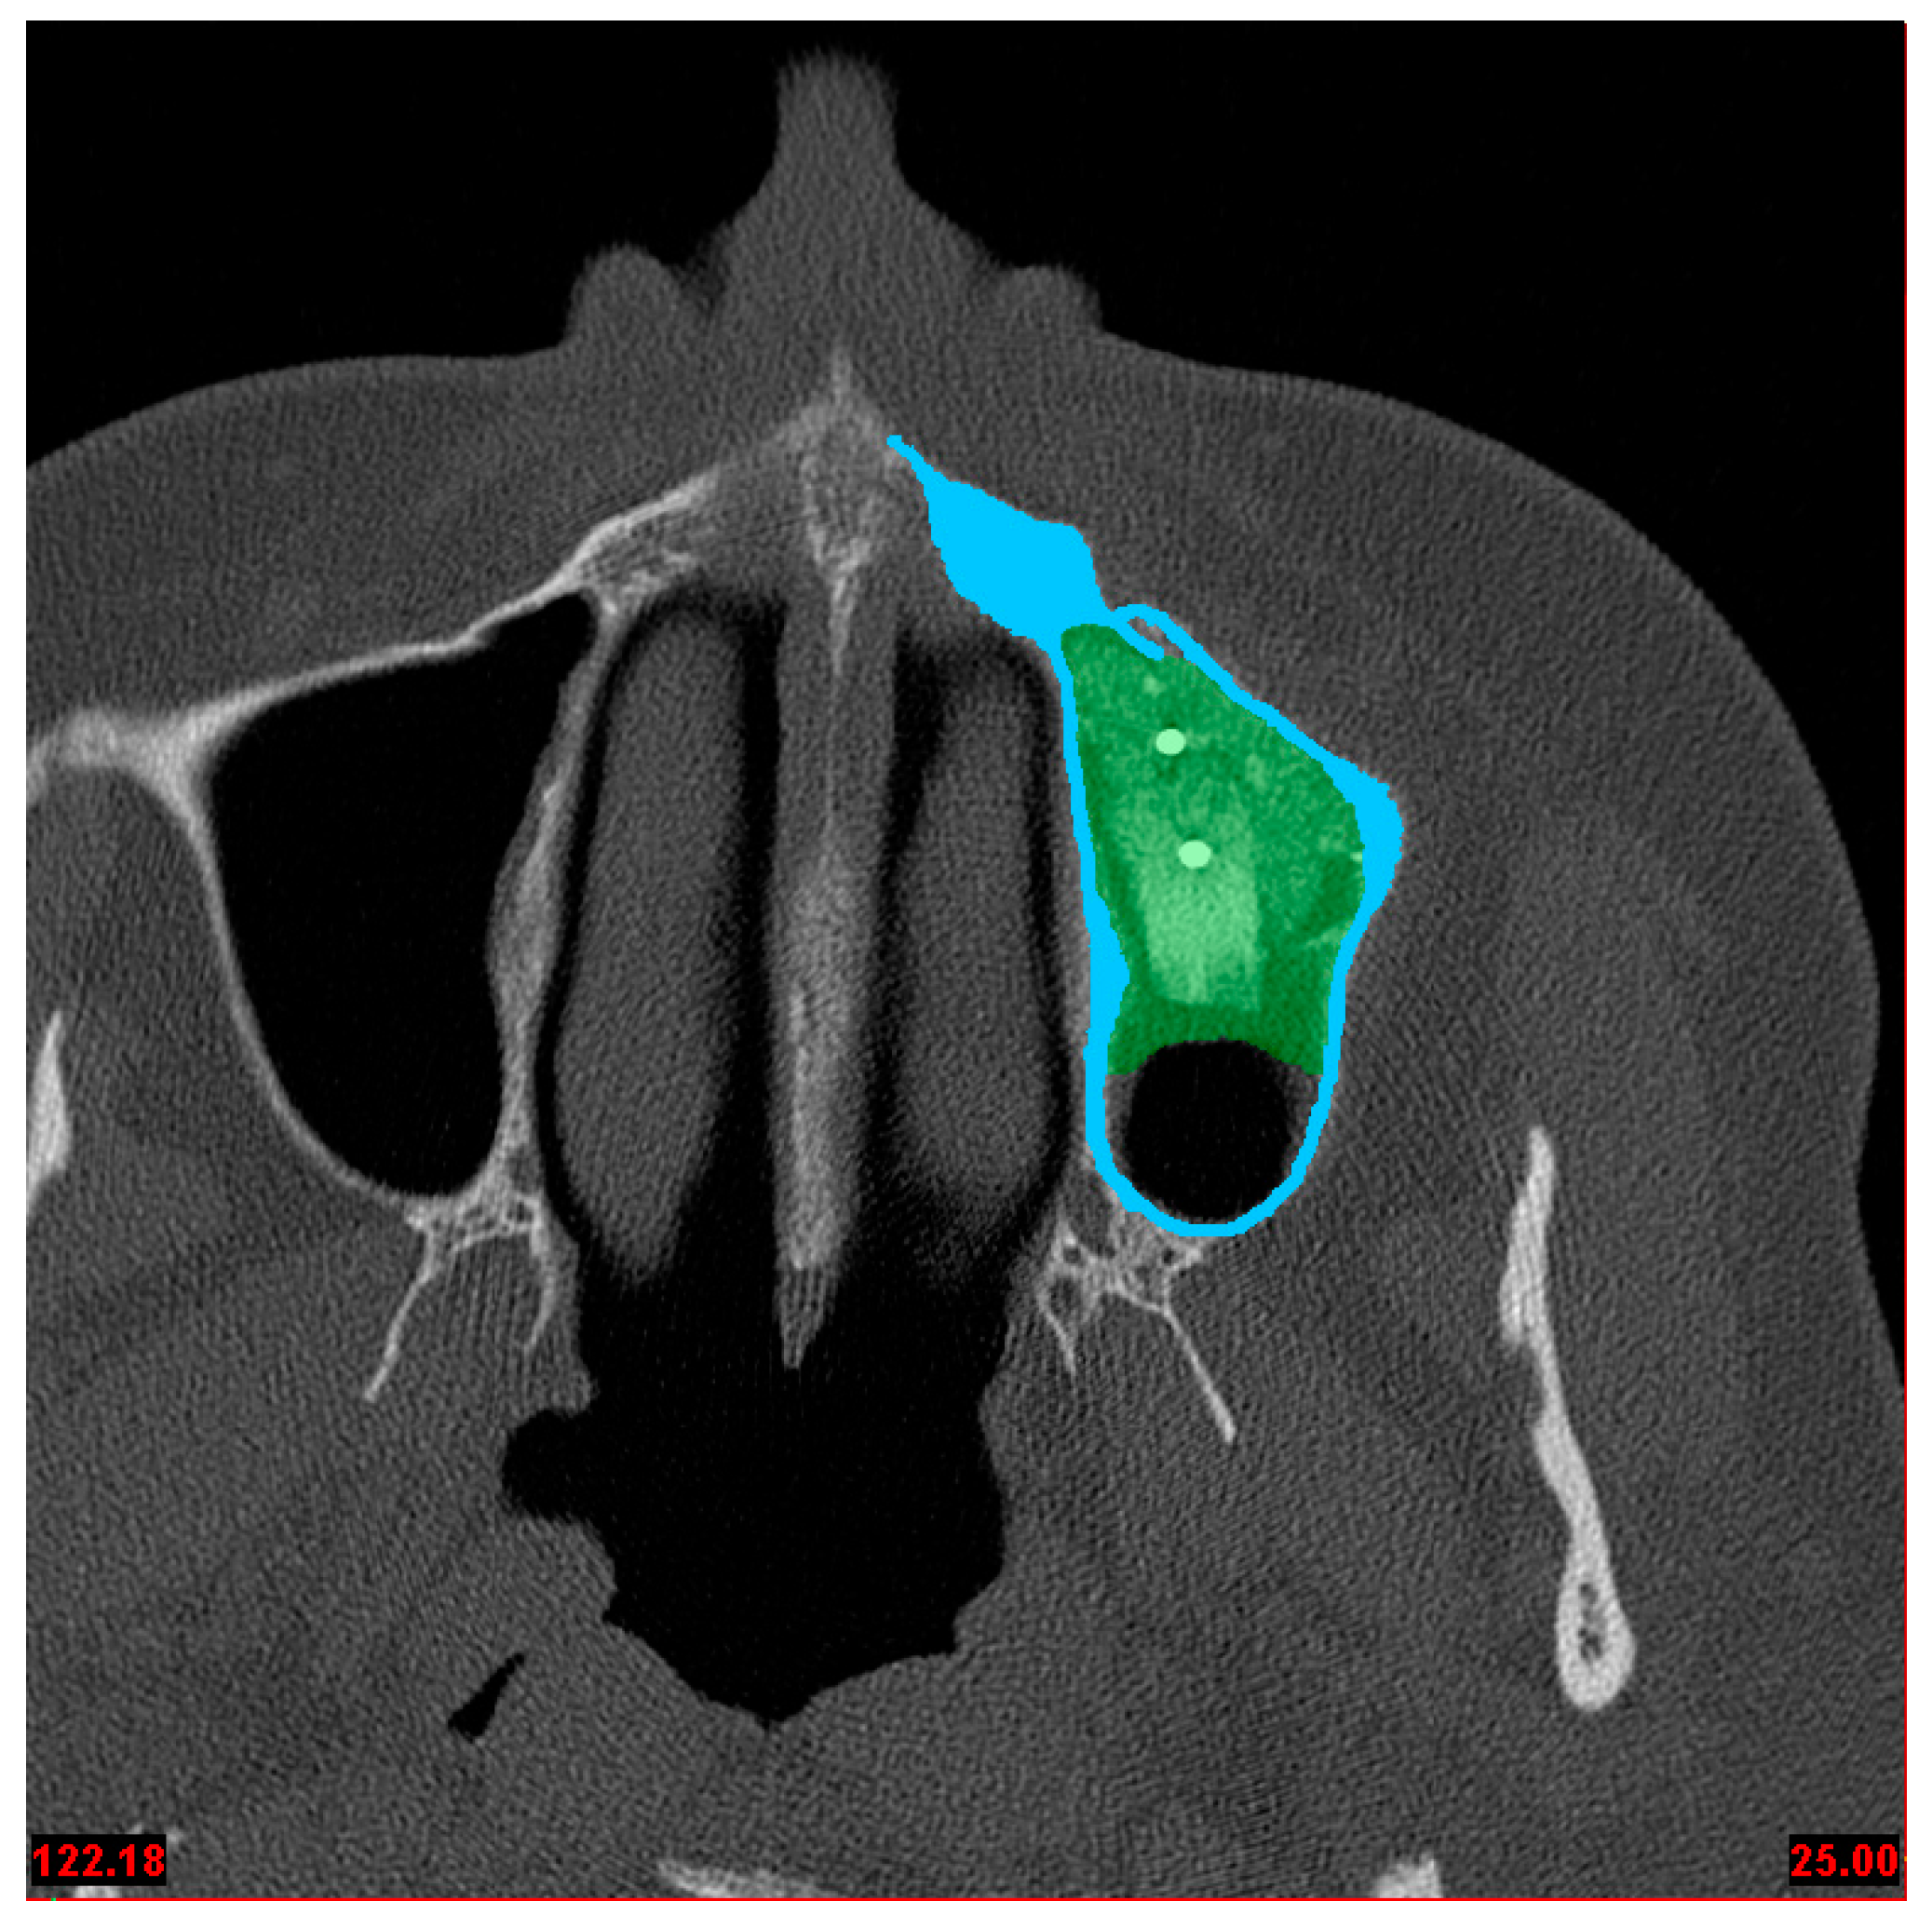

Figure 1.

CT of the augmented left maxillary sinus with two fixing screws and the bone graft block. Blue indicates segmented compact bone; green indicates segmented augmented bone.